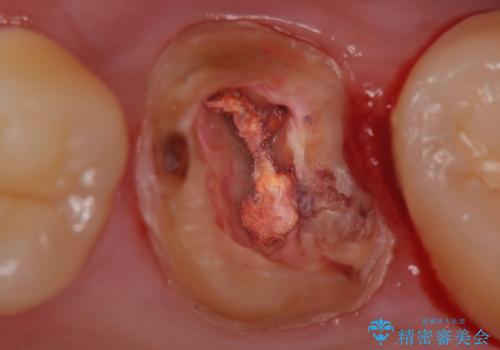

- 奥歯の樹脂の色が気になるとのことで来院されました。

変色しない材料での治療をご希望されたためセラミックインレーでの治療をしていくこととなりました。

継ぎ接ぎになった樹脂の詰め物から一塊のセラミックインレーに置き換えることで着色や二次う蝕のリスクを抑えます。

- 天然歯を削ります